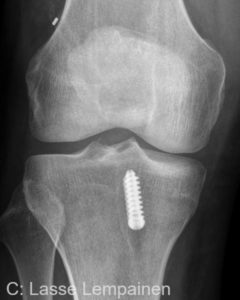

Leikkauksen jälkeen polvesta otetaan usein röntgenkuva, jolla varmistetaan eturistisiteen oikea asemointi (kuvat 10 ja 11).

- Kuva 10

- Kuva 11